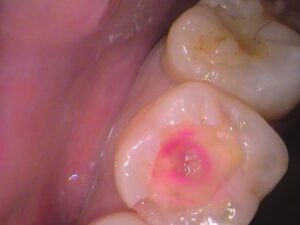

う蝕検知液という虫歯を染色するお薬を塗ってみましょう。

赤く染まっている箇所が虫歯のところです。

詰め物の中がほとんど虫歯で広がっています。